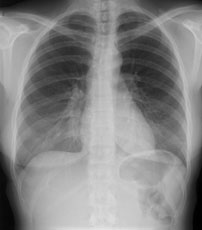

Radiologie Quiz 48

Eine 36-jährige Patientin kommt zu Ihnen in die Praxis. Sie berichtet über einen grippalen, fieberhaften Infekt, seit einer Woche bestehend.

In der Lungenauskultation sind Rasselgeräusche beidseits basal zu hören. Bei einem CRP von 160 mg/l veranlassen Sie ein Thoraxröntgen mit der Frage nach Infiltrat.

Hier sehen Sie die Bilder:

Wie lautet Ihre Diagnose?